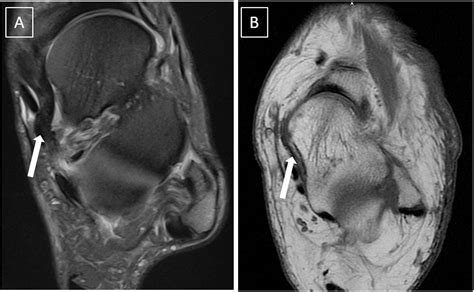

Mri Spring Ligament. Web mri findings present in surgically proven spring ligament tears include an abnormal spring ligament caliber, signal intensity,. Web the presence of waviness, discontinuity, and abnormally high signal intensity of the spring ligament complex.

Web mri findings present in surgically proven spring ligament tears include an abnormal spring ligament caliber, signal intensity,. Web the presence of waviness, discontinuity, and abnormally high signal intensity of the spring ligament complex.